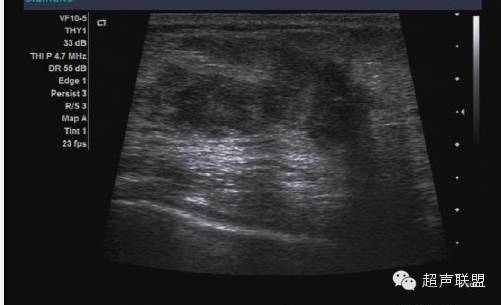

3. 振荡多普勒成像

振荡多普勒成像或声学弹力图,是从著名的震颤乳腺超声技术派生而来的(如图5所示)。在震颤检查中,用彩色或功率多普勒进行乳腺成像的同时要求病人发出声音。乳腺中松软的部份振动较大,而癌变区域和其它较硬的组织振幅小,形成影像中色彩较弱的区域。这样原来在B超中声学特性一致的区域,因其结构的疏密变得可以区分。振荡弹力图或振荡多普勒成像与此类似,不同的是用一个单独的传感器产生振荡。该传感器可产生不同的振荡频率,而成像系统里的定量功率多普勒算法可以计算出组织在每一频率上的振荡量。振荡多普勒成像用于观察组织的粘弹特性。

对于20个病人的初步研究表明,病变区域的振荡量随频率变化的规律十分复杂。病变肿块区并不是在任一频率都会比周围组织振荡得小。这或许能够解释震颤法临床所得的结果变化不一。不同的病人发出不同的音调,在特定频率下,病变区的振荡不一定与周围组织不同。而且,良性肿块振荡量随频率变化的范围很大。相反癌变区表现出少量的振荡,而且随振荡频率的变化很小。

利用良性和恶性肿瘤的振荡差异,我们有可能准确地诊断大多数良性肿瘤而不会把癌症误断为良性。图6所示为两个肿瘤的频谱图,一块为良性,另一块为恶性。良性肿瘤的振荡变化量随频率范围的增大而增大,而恶性的振荡变化量随频率变化很小,而且恶性肿瘤整体信号强度都很弱。值得注意的是,在某一频率范围内,恶性与良性病变的振动强度相同,使之变得不可区分。